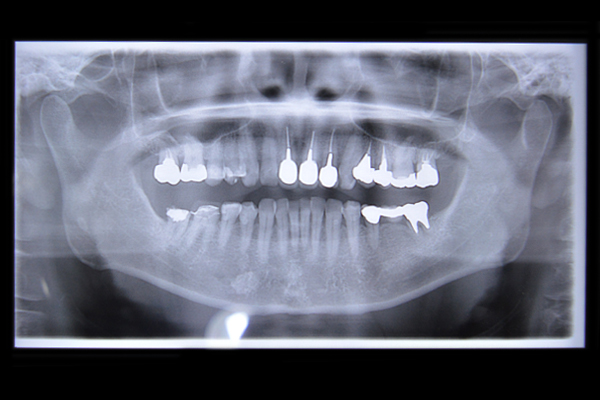

神経がしんでしまったり、神経まで及ぶむし歯にかかってしまった歯には根管治療(根の治療)が必要な場合があります。

前に受けた根管治療が不完全で根の周りに炎症を起こしている場合も、根管治療が必要になります。

根管治療は、歯の修復物(詰め物や被せ物)がない状態で行いますので、新規に修復を行う場合で根管治療の必要な場合は、良質な根管治療が歯の長期的な健康の為には必須です。